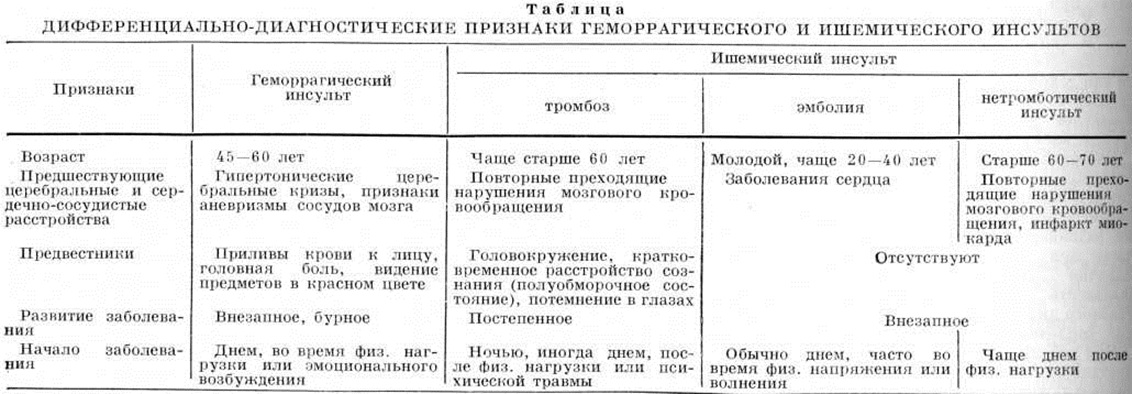

Дифференциальная диагностика геморрагического и ишемического Инсульт — смотри полный свод знаний таблицу.

| ||

| ||

| ||

| ||